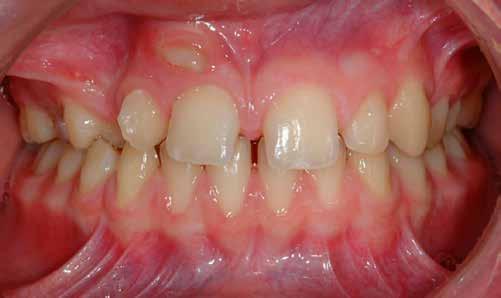

használja, hogy a páciens 7. ábra: Frontális nézet – okklúzióban. 8. ábra: Jobb bukkális nézet – okklúzióban. 9. ábra: Bal bukkális nézet – okklúzióban. 10. ábra: Felső okkluzális nézet – tükör. 11. ábra: Alsó okkluzális nézet – tükör.

ajkait oldalra és kifelé, a fogaktól és az ínytől távolabb húzza vissza. Az összes fog és a kapcsolódó szövetek láthatóvá tételéhez maximális látómezőre van szükség. A felvételt az arc középvonalához és a központi metszőfogakhoz képest 90°-ban kell készíteni. Az okklúziós síkot a páciens meglévő okklúziójának megfelelően kiegyenlítve. A Ring-Flash nagyban segíti a minőségi fénykép elkészítését, mivel biztosítja a lehető legjobb megvilágítást árnyékmentesen, különösen a szájüreg mélyebb részein és a bukkális vestibulumokban (7. ábra).